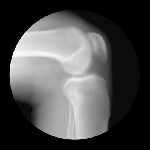

JOINTS IN MOTION

Cameron Drake of San Francisco has created a collection of magnificent images showing joints in motion. He was aided by orthopedic physician Dr. Noah Weiss and the finished product is completely amazing. If you’d like to know more about the project, please check out Drake’s blog.